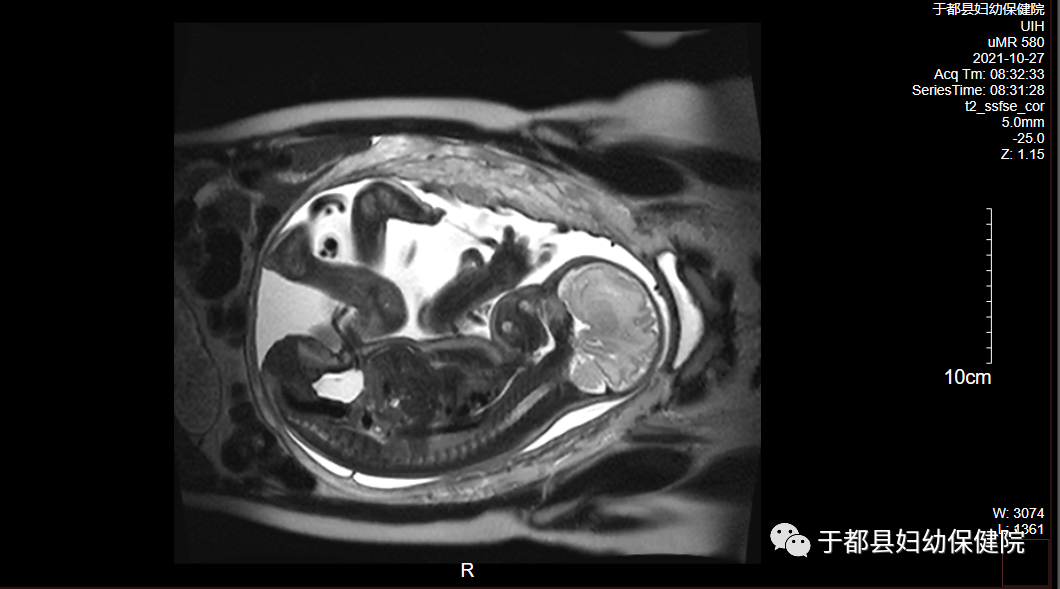

胎儿检查:胎儿磁共振(MR)是除超声检查之外的另一种重要的产前影像学检查方法,产前筛查的重要补充手段。具有良好的软组织及空间分辨率、多平面成像、广阔的视野、无电离辐射损伤等优势。MR不受母体、骨骼及羊水等影响,对胎儿各系统,尤其是中枢神经系统解剖结构及病变的显示明显优于超声;其次MR对胎儿组织的定性较好,可对胎儿病变诊断提供更多的信息。MR与超声检查有互补作用,两者相结合,能提高诊断率。